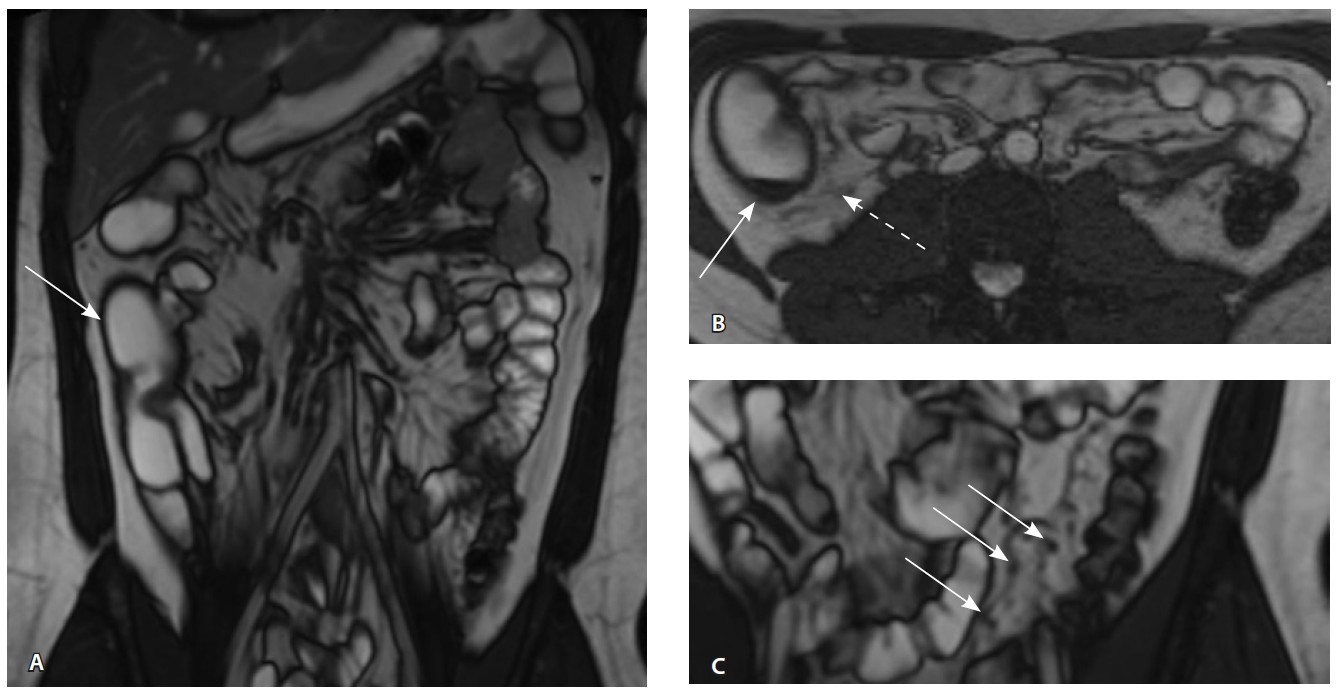

Рис. 3. Магнитно-резонансная энтерография, Т1-взвешенное изображение после внутривенного контрастного усиления (гадобутрол, 5 мл): А – фронтальная проекция, Б – аксиальная проекция. Наблюдается выраженное усиление интенсивности сигнала от восходящего отдела ободочной кишки (стрелка), усиление сигнала от окружающей клетчатки (пунктирная стрелка)